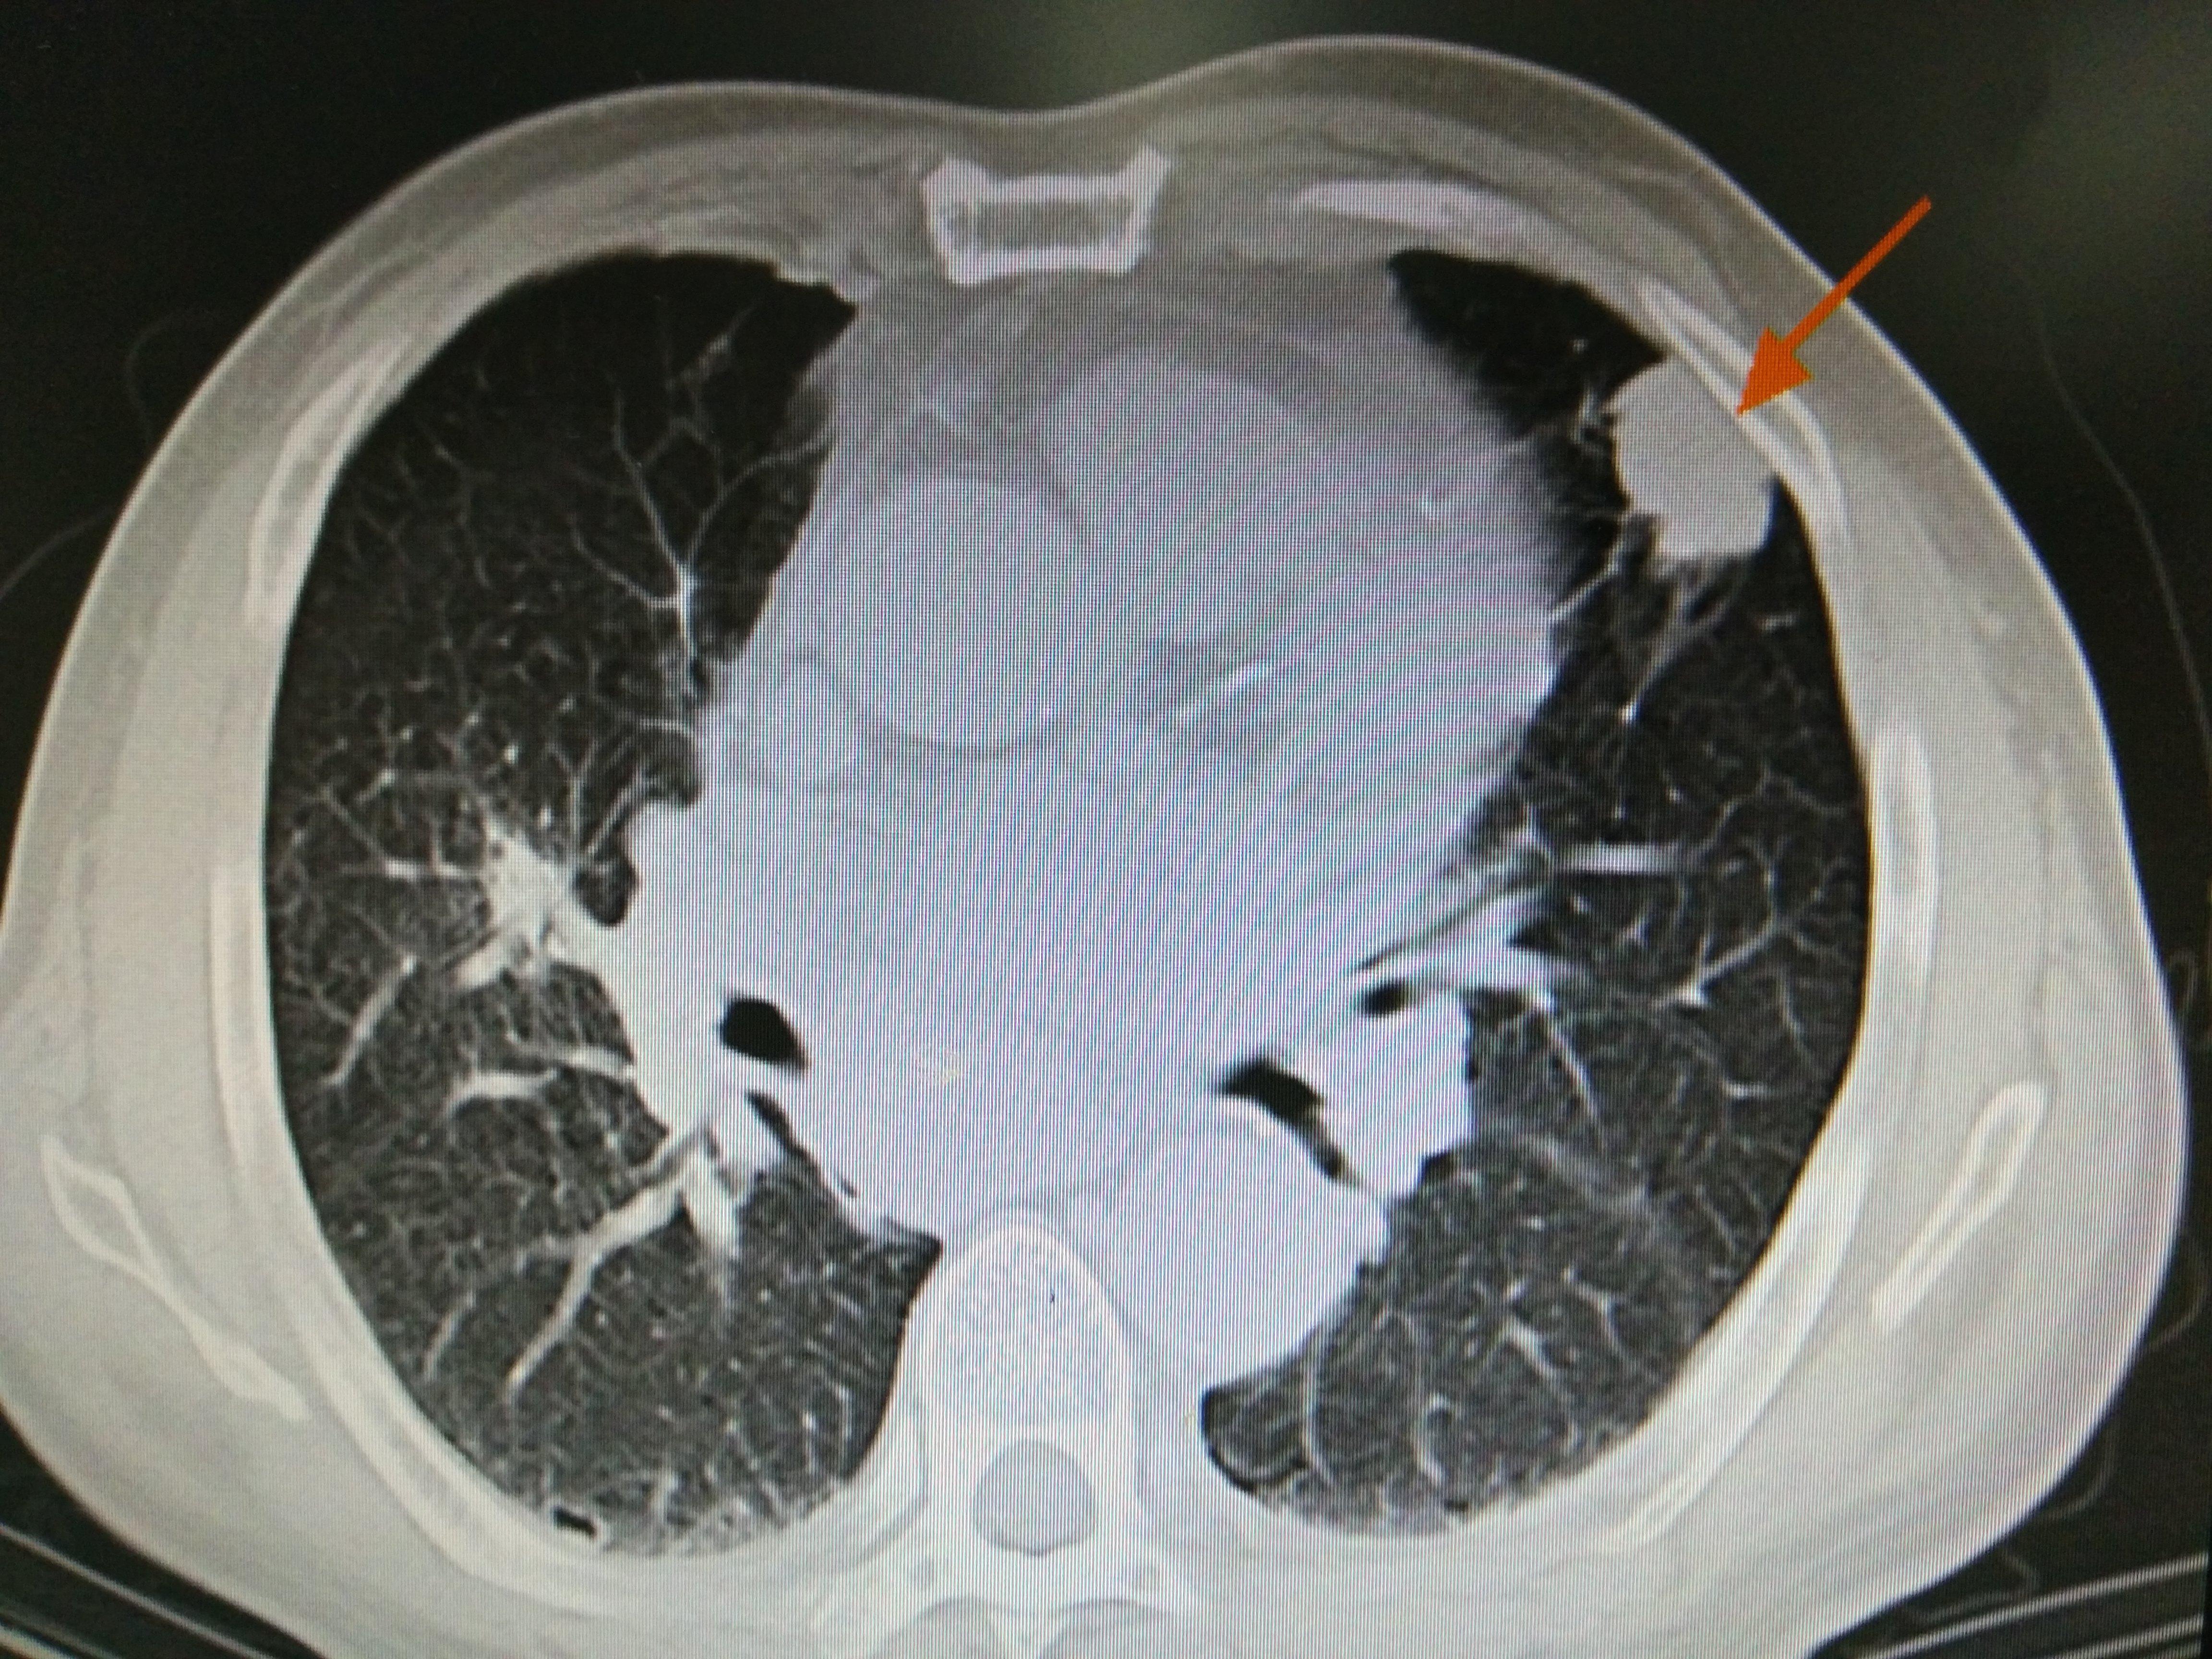

这是一位晚期肺癌的患者,平时生活很不规律,抽烟喝酒,什么刺激来什么。钱是赚了不少,可惜身体早早就不行了。刚过50岁,就发现了肺癌,而且是恶性程度最高的,低分化癌!!肺上病灶4cm,可是已经骨转移了。开刀当然不现实了,刚开始他想放疗,可是一看要20几次,还有放射性肺炎,马上打了退堂鼓。而且这个时候,因为病灶侵犯胸膜,出现剧烈胸痛,要吃吗啡才能缓解。怎么办?怎么办?怎么办!患者家属找到我的时候,无奈的问我。

肿瘤比较局限,贴近胸膜,引起胸痛。